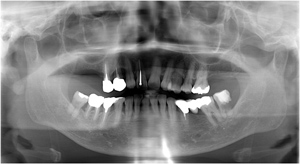

1﹒專為牙醫設計的專業牙科影像軟體,結合所有牙科影像並提

......供各種影像的運用。

2﹒可快速將拍攝畫面導入影像軟體中,提供多項影像的操作功

......能例如:植牙、矯正.....等。